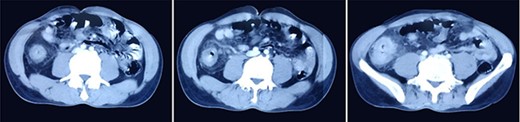

A 51-year-gentlemen and a smoker visited our institute with a history of abdominal pain, predominantly over the umbilical area, constant in nature, associated with anorexia, back pain and occasional chest pain for about 1 year. Besides pallor, other examination findings were grossly normal. His body mass index was 17 mg/m2. The comprehensive blood panel, renal function test and liver function test yielded normal findings. USG of abdomen and pelvis showed thickened cecum and terminal ileum with few adjacent mesenteric lymph nodes likely to be an infective/inflammatory pathology along with coexisting right nephrolithiasis. Intestinal TB was suspected and further investigations were done but reported negative Mantoux test, AFB smear and normal chest X-ray findings. Colonoscopy showed ulcero-proliferative growth in the cecum and descending sigmoid junction with punch biopsy from the cecal growth showing mitotic lesion suggestive of carcinoma colon (Fig. 1). A repeat colonoscopic biopsy of the cecal growth suggested diffuse active colitis. Computed tomography (CT) revealed segmental asymmetrical circumferential mass-like wall thickening of the cecum and ascending colon over the length of 7.6 cm causing luminal narrowing with enhancing soft tissue extension into the adjacent pericolic fat with loss of fat plane with the right psoas major muscle, pericolic fat stranding along with thickening of adjacent peritoneal lining (Fig. 2). The presence of multiple homogeneously enhancing pericolic, ileocolic, superior mesenteric artery and para-aortic groups of lymph nodes suggested colon carcinoma (T4aN2b). It also revealed a small iso-dense lesion showing homogeneous enhancement on the arterial phase in segment VII of the right lobe of the liver abutting capsule suggestive of metastasis. Carcinoembryonic antigen (CEA) was found to be slightly raised (7 ng/dl).

CT images showing segmental asymmetrical circumferential mass-like wall thickening of the cecum and ascending colon over the length of 7.6 cm causing luminal narrowing with enhancing soft tissue extension into the adjacent pericolic fat with loss of fat plane with the right psoas major muscle, pericolic fat stranding along with thickening of adjacent peritoneal lining.